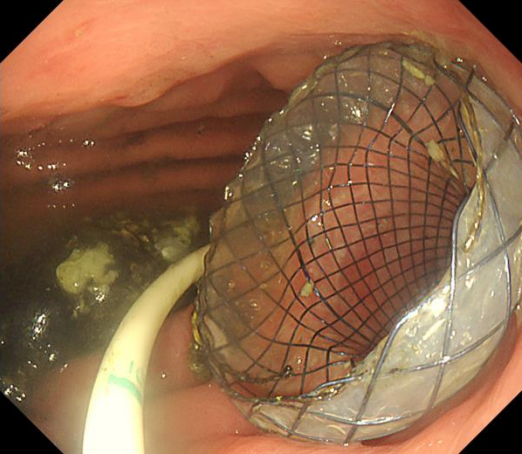

术后四周,孙家琛为李阿姨取出LAMS支架,并夹闭了创面。经过治疗,李阿姨顺利出院,出院前复查

左图取出支架后经胃观察包裹性坏死腔,为新鲜肉芽组织;右图胃镜观察取出支架后的创面